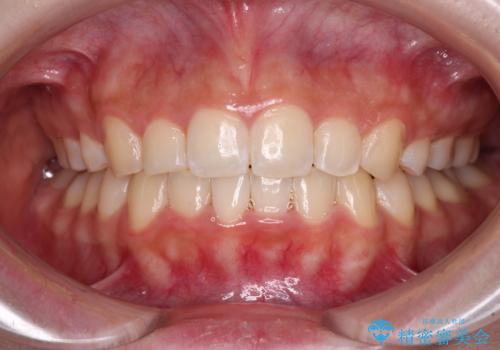

治療途中で出産されたこともあり、当初予定よりも終了までに期間がかかってしまいました。

舌を前方に突出する癖があったため、上下前歯がなかなか接触しなかったことも治療期間が伸びた要因です。